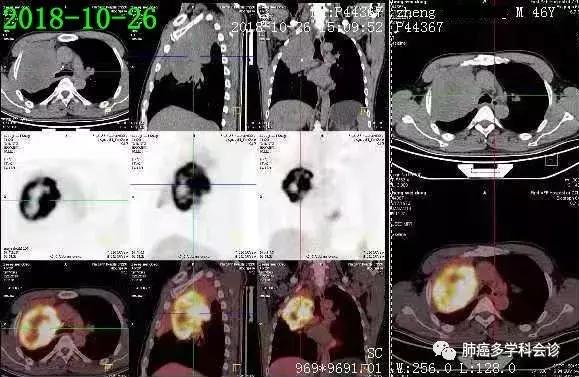

患者郑WD,男,46岁,吸烟20余年,平均20支/天。2018年10月因“咳痰、胸闷20余天”在当地医院就诊,胸部CT发现右上肺占位。支气管镜病理活检(2018.10.24):鳞癌, PD-L1高表达(+约90%)。

PET-CT示(2018-10-28):右肺上叶近肺门软组织肿块代谢不均匀活跃,远侧肺组织不张;右侧锁骨上/下及纵隔(2R)和4L 小淋巴结淋巴结代谢稍活跃。